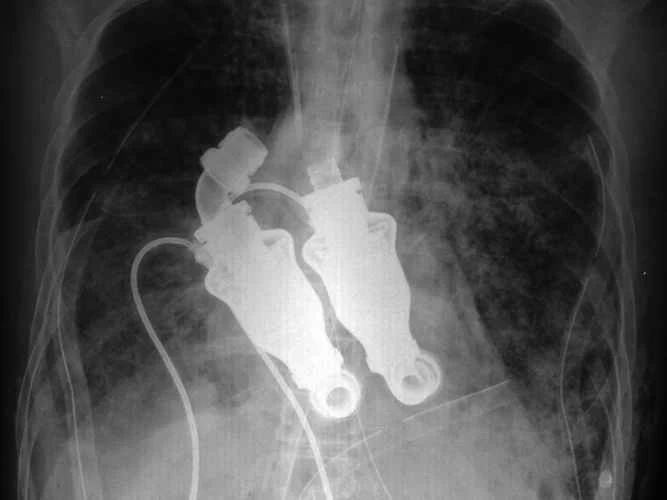

私たちは生物医学や工学を頻繁に取り上げていますが、時々こんな疑問が湧きます。もし私が、おそらくは恐ろしい手足切断や内臓損傷の事故に遭ったために、もろい肉体を再構築し、手足、関節、感覚、臓器を最先端のバイオニクス機器に置き換えるとしたら、一体何を手に入れるのだろうか?オリンピックレベルのレースで短距離走者が使うような人工下肢が欲しいだろうか?それとも、自然な脚と同じように坂を登れる電動の脚が欲しいだろうか?私は、自分が身に着けたい、あるいは装着したいバイオニックボディパーツを15個リストアップしました。

これらの身体部位の中には、既に利用可能で、命を救ったり、生活を楽にしたりするものもあれば、プロトタイプや概念実証の段階に過ぎないものもある。既存の身体部位を可能な限り犠牲にすることなく置き換えるように設計されたものもあれば、生身の肉体よりも優れた利点をもたらすものもある。これがバイオニクスの現状、そして近未来の姿である。